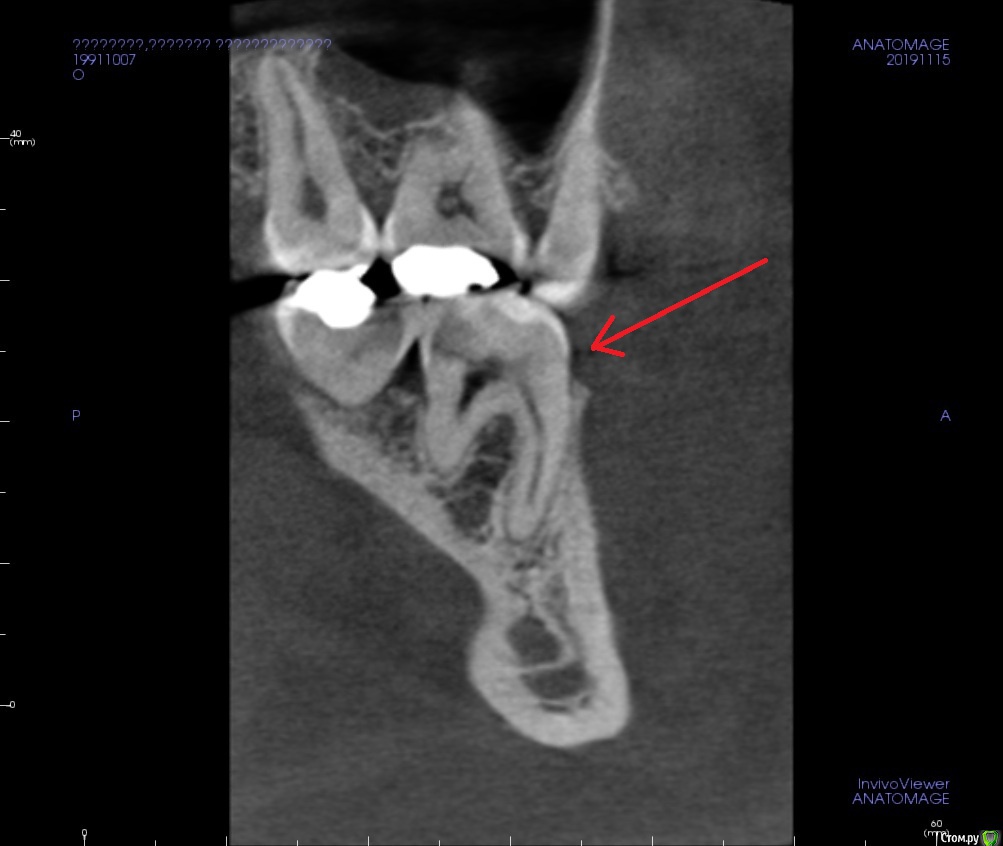

Verta Опубликовано 21 ноября, 2019 Поделиться Опубликовано 21 ноября, 2019 (изменено) Вечером разболелась половина лица, подумала на начинающийся гайморит или режущийся зуб мудрости. На 4 день боль локализовалась в нижней 6. Зуб пломбированный лет 15 назад, ранее не беспокоил, стал реагировать на холодное: рентген, пульпит. После наложения пасты реакция на холодное пропала, но при давлении на зуб сильная боль, также боль при давлении на десну под зубом только с внутренней стороны. Через 3 дня обратилась с болью- пасту переложили. После очередного приступа боли сделала КТ зуба, третий врач предположила, что это реакция на пасту. На лечении при прохождении одного канала была опять эта знакомая боль. Контрольный снимок показал правильно запломбированные каналы. И вот, спустя неделю, зуб сильно болит при накусывании, никаких изменений на дёснах нет, четыре врача не видят причины. Что делать? Снимки сделаны до лечения, ещё заложена паста Изменено 21 ноября, 2019 пользователем Verta Ссылка на комментарий

Verta Опубликовано 22 ноября, 2019 Автор Поделиться Опубликовано 22 ноября, 2019 Снимок Ссылка на комментарий

krokomot Опубликовано 22 ноября, 2019 Поделиться Опубликовано 22 ноября, 2019 если боли не проходят, распломбировывать , снова мыть снова паста на основе гидроокиси кальция, затем постоянная пломбировка. по кт найти все каналы и возможные ответвления. 1 Ссылка на комментарий